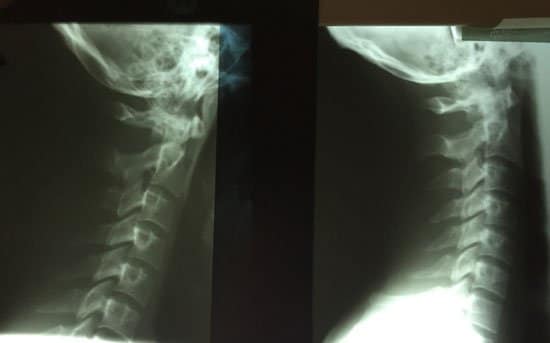

Chiropractic adjustments are an effective treatment option for whiplash that targets the root cause for pain: the spinal misalignment. Our Boca Raton whiplash chiropractor uses diagnostic exams to determine the precise location of a subluxation or cervical spine misalignment following a whiplash injury. Chiropractic adjustments bring proper alignment back to the cervical spine, relieving nerve and muscle compression for long-lasting pain relief and increased mobility. In fact, see the below picture* of an actual whiplash patient (2016) of before (left side) and after (right side). You can see considerable improvement of the spine back to it’s normal curvature on the right. Chiropractic can help!

Whiplash patient (left-before) and treatment (right-after). Normal curvature achieved with chiropractic.